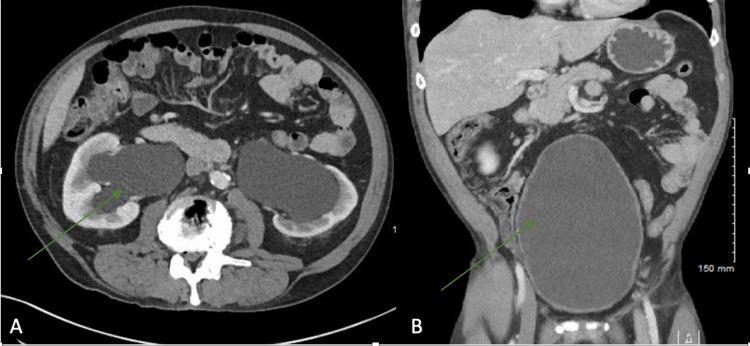

Kidneys influence the production of red blood cells by secreting most of the erythropoietin (EPO) in adults. Consequently, renal diseases often impact erythropoiesis and hemoglobin levels. Chronic kidney diseases lead to anemia due to EPO deficiency. However, erythrocytosis can occur in patients with cystic diseases of the kidney and renal artery stenosis due to upregulation of hypoxia-inducible factors (HIFs) and increased EPO production. Here, we present a patient with secondary polycythemia who was found to have atonic bladder and hydronephrosis. Resolution of hydronephrosis led to the reversal of erythrocytosis, highlighting the intricate regulation of red cell production.

在成年人中,肾脏通过分泌大部分促红细胞生成素(EPO)来影响红细胞的生成。因此,肾脏疾病常常会影响红细胞生成和血红蛋白水平。慢性肾脏疾病会因EPO缺乏导致贫血。然而,由于缺氧诱导因子(HIFs)上调和EPO生成增加,患有肾囊性疾病和肾动脉狭窄的患者可能会出现红细胞增多症。在此,我们报告一名患有继发性红细胞增多症的患者,该患者被发现存在无张力膀胱和肾积水。肾积水的缓解导致红细胞增多症的逆转,突出了红细胞生成的复杂调节机制。